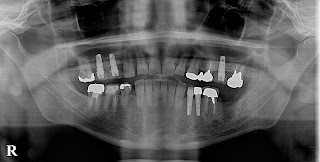

③レントゲン撮影

(パントモX線・頭部X線・頭部X線規格写真正面側面など)